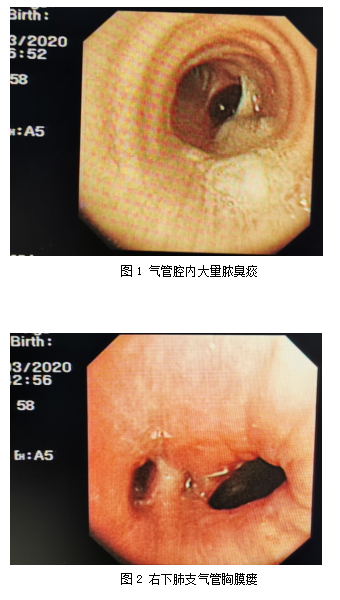

该名患者为六十多岁的男性,诊断右下叶肺癌术后一年余,右下叶支气管胸膜瘘已半年,曾在区内多家大型医院治疗。因身体条件太差,不能耐受手术,其他医院医生们的建议都是保守治疗,但效果均不理想。

患者胸壁已形成瘘口,长期流脓,反复咳嗽咳脓臭痰,气味难闻,整个家庭苦不堪言。辗转多处最后来到桂医附院呼吸与危重医学科,找到了马礼兵,希望尝试呼吸微创介入治疗。

入住呼吸与危重症医学科后,马礼兵团队详细回顾了患者的诊疗过程,并充分评估患者目前病情,结合胸部影像资料及支气管镜检查等结果,经过介入团队多次讨论,初步论证确定了患者的适宜介入手术方案;后经过与患者及家属反复沟通后,决定大胆尝试,利用这一创新术式以期解决支气管胸膜瘘问题,也可更好的处理胸腔感染问题。

马礼兵认为:该患者有不规则、多个胸膜瘘口,最长径超过10mm,如使用医用胶粘合固定性差,咳嗽容易脱落;局部注入硬化剂对于瘘口<3mm者疗效尚可,瘘口大者失败率很高。右下叶置入覆膜支架或硅酮支架需要个体化定制,因疫情影响资源可及性差,而且还有可能影响健康的右肺中叶通气,也比较难固定,所以综合权衡后选择尝试室间隔封堵器进行封堵。室缺封堵器边宽腰短,置入后一般不会移位,也不容易会影响中叶通气。